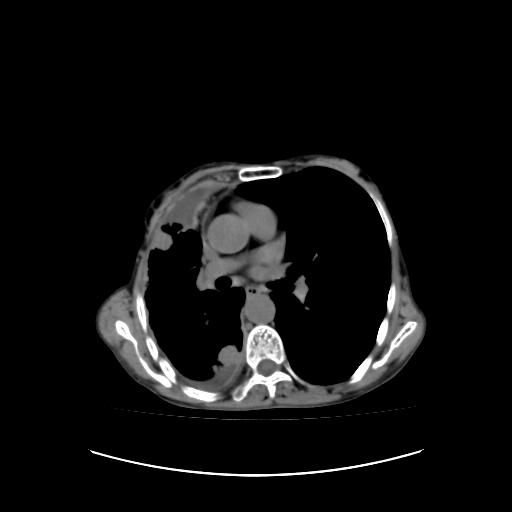

标题: CT16930:女 59 胸痛6个月 胸水脱落细胞学见瘤细胞 [打印本页]

标题: CT16930:女 59 胸痛6个月 胸水脱落细胞学见瘤细胞

可见多发肺内病灶,且胸膜病灶较多有圆球状而非丘状,多考虑胸膜转移瘤伴胸腔积液,右侧胸廓缩小固定,且部分病灶呈丘状,尚不除外恶性胸膜间皮瘤伴肺内转移

右侧胸膜增厚,局部呈结节状增厚,右侧胸腔少量积液。双肺未见确切肿块影。纵隔未见淋巴结肿大。气管、支气管通畅。考虑右侧胸膜间皮瘤(恶性?)可能性大。不除外癌性胸膜炎。

恶性胸膜间皮瘤伴肺内转移可能性大;或胸膜、肺内均为转移瘤,左肺下叶亦见多发小结节影。

右侧胸廓塌陷,右侧胸膜广泛增厚并见多发胸膜结节,右侧少量胸腔积液并包裹。

右侧广泛胸膜增厚,局部呈结节状增厚,右侧胸腔少量积液。双肺未见确切肿块影。纵隔未见淋巴结肿大。气管、支气管通畅。考虑右侧胸膜间皮瘤(恶性?)可能性大。支持!

右侧胸膜转移瘤,原发灶可能就在在右肺,另外建议检查右侧乳腺.

右胸腔结节均考虑来自胸膜(部分来源于叶裂),考虑胸膜间皮瘤或转移瘤.